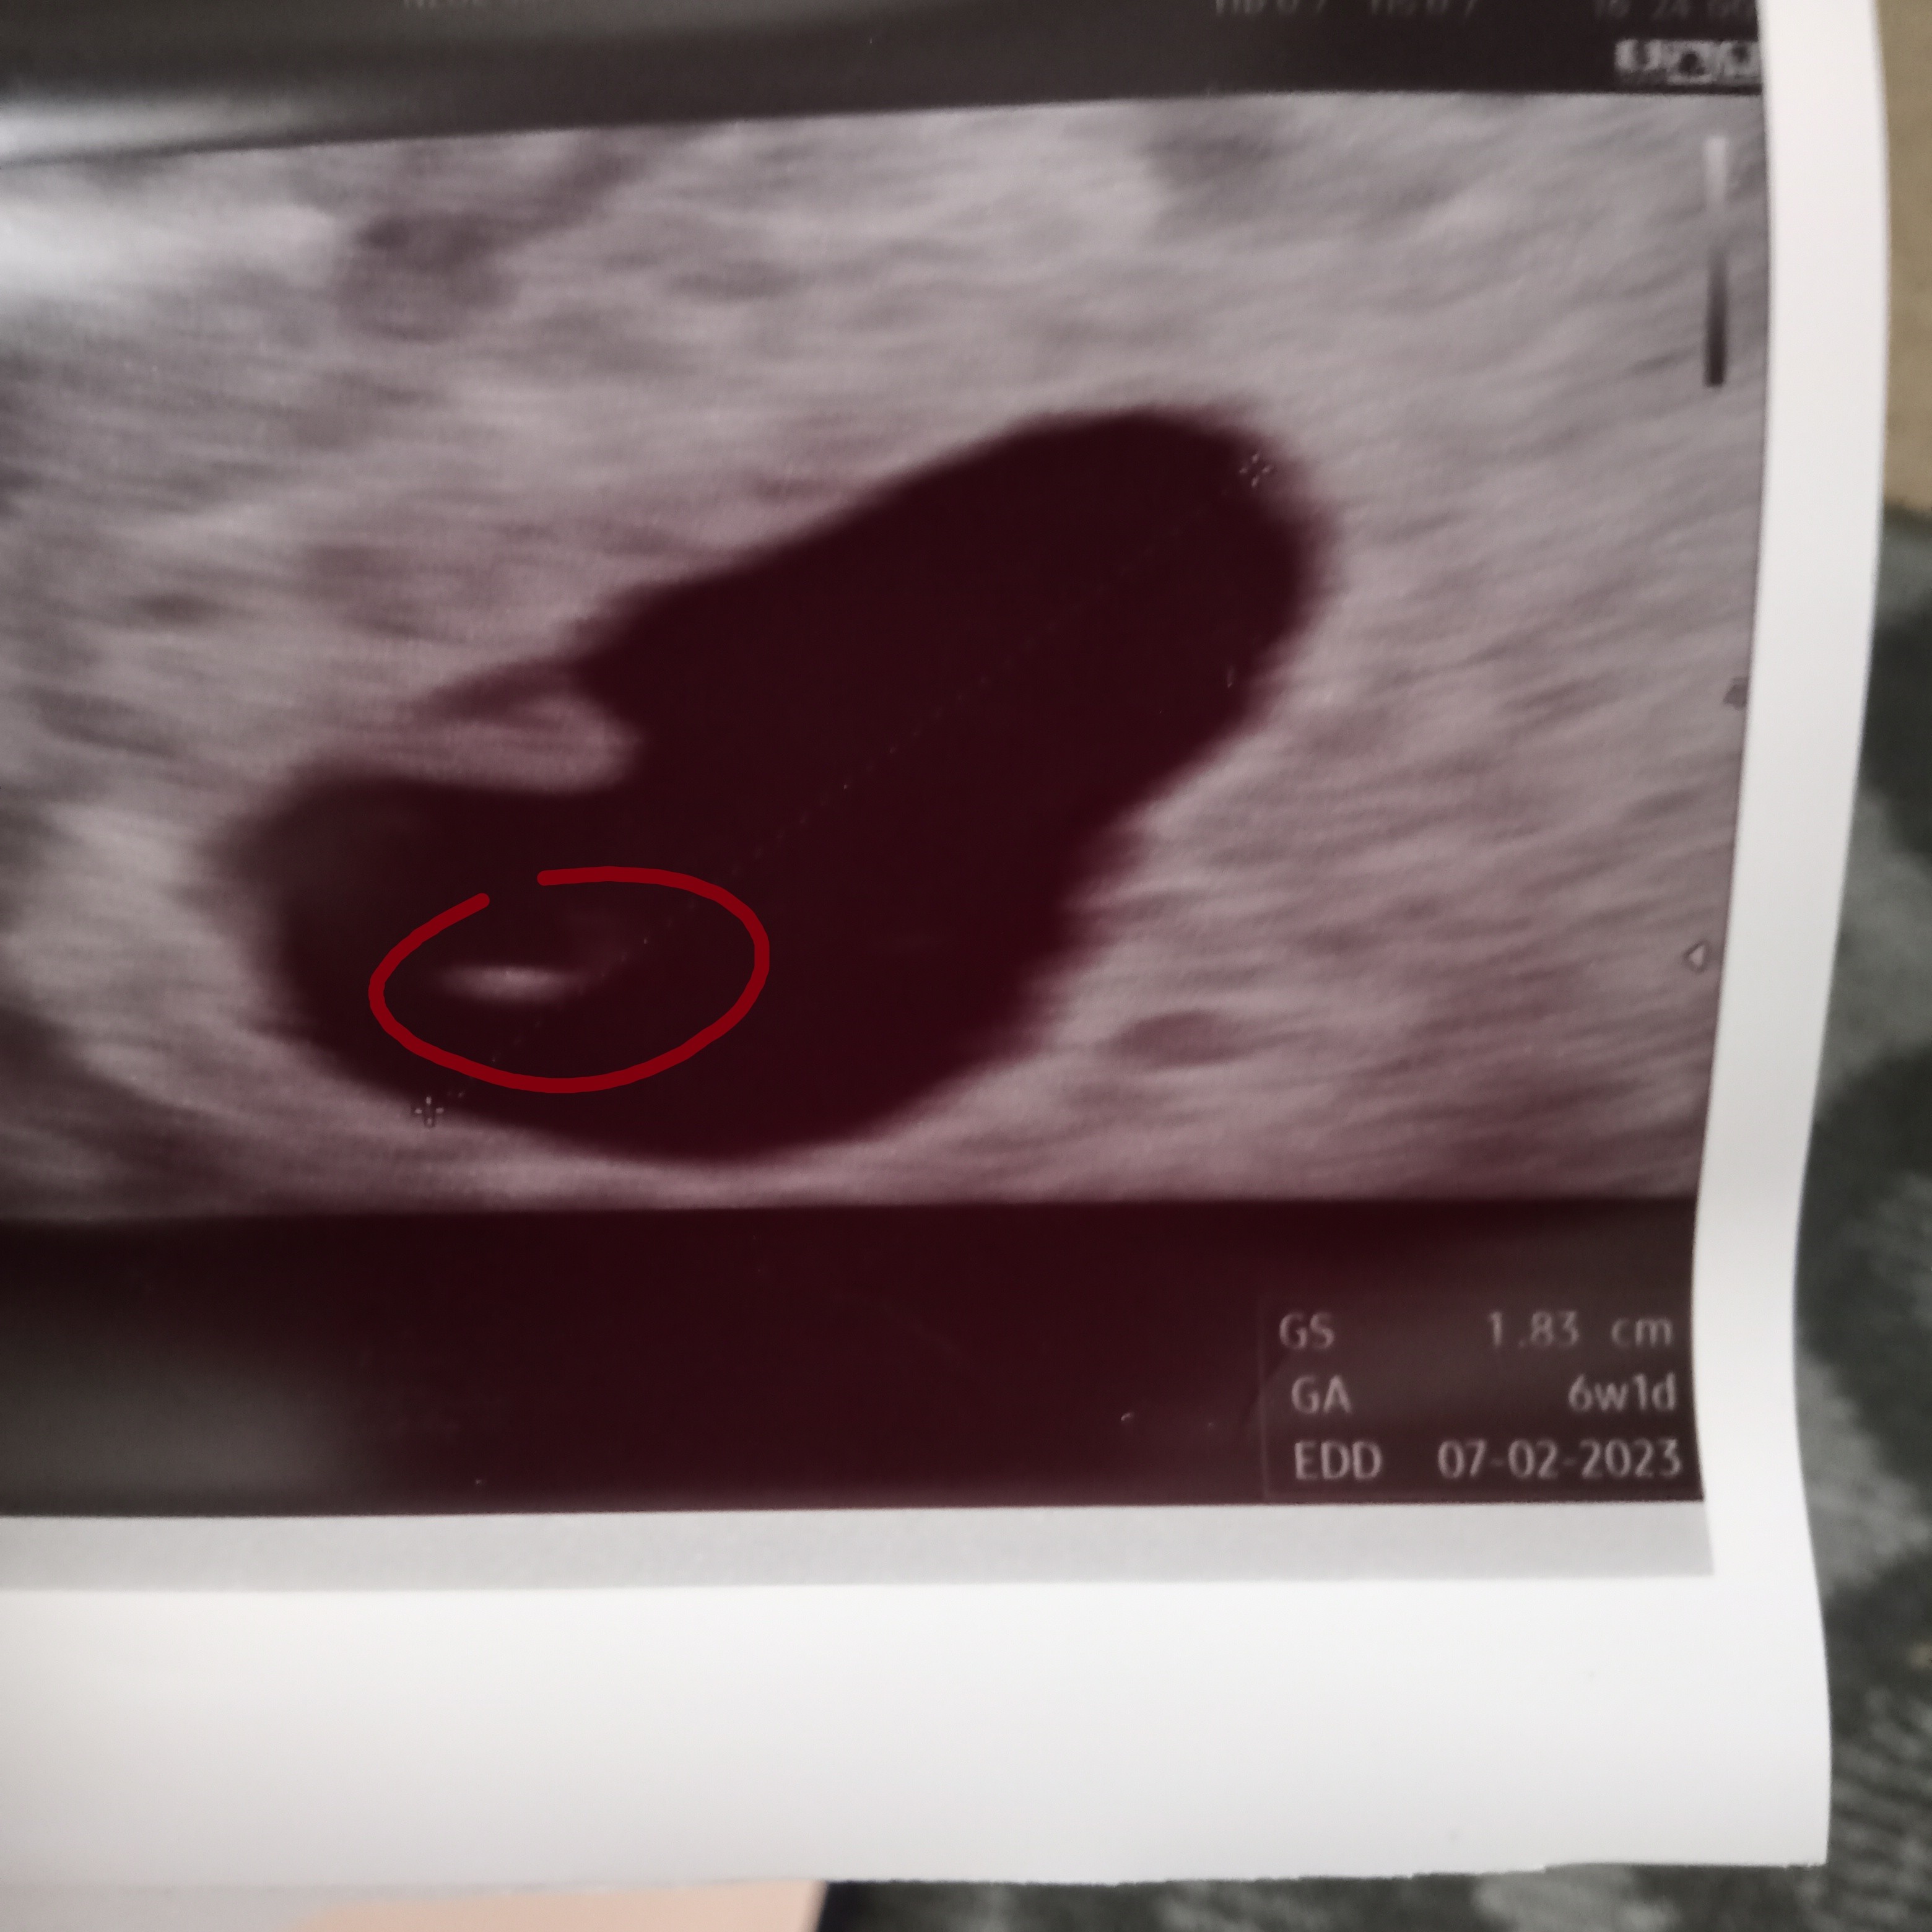

Interpretacja USG 6+1

Może któraś z was wie co to jest to zaznaczone na zdjęciu przeze mnie. Pytam bo w pozostałych ciążach jakoś inaczej to wyglądało. Może głupie pytanie ale nie daje mi to spokoju. Bez hejtu proszę. Dodam że to zdjęcie z 6+1

To czarne duze to pecherzyk ciazowy. A to, co zaznaczylas, to moze byc cien prcherzyka zoltkowego, z ktorego odzywia sie zarodek na poczatku ciazy lub jakis fragment blon plodowych. Lekarzem nie jestem, wiec prosze nie brac tego na 100%.